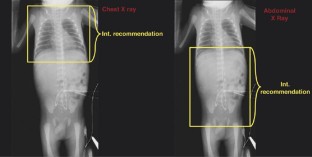

During a 1-month period, 157 consecutive neonates from five level-III NICUs were recruited for this study. The mean birth weight was 1747±911 g (range: 564–4080 g), and gestational age was 31.6±3.6 weeks (range: 24–41 weeks). A total of 500 radiographs were performed including chest (68%), abdomen (17%) and combined chest and abdomen (15%). The average number of radiographs taken per infant was 4.2±3.6 (range: 1–21). Unintentional inclusion of body regions other than those ordered was determined by comparing the areas that should be included in the radiation field according to International recommendations, to those that appeared in the actual radiograph.

A comparison of the recommended borders to the actual boundaries of the radiographs taken show an additional exposure to radiation in all three procedures: 85% of chest radiographs also included the whole abdomen, 64% of abdomen radiographs included both thigh and upper chest and 62% of chest and abdomen radiograph included the thigh. (The range in all procedures was from ankle to upper head.) Between 2 and 20% of the relevant targeted body tissues were not included in the exposed fields resulting in missing data. The gonads of both sexes were exposed in 7% in all chest X-rays. Among male infants, the testes were exposed in 31% of plain abdomen radiographs and 34% of chest and abdomen radiographs.